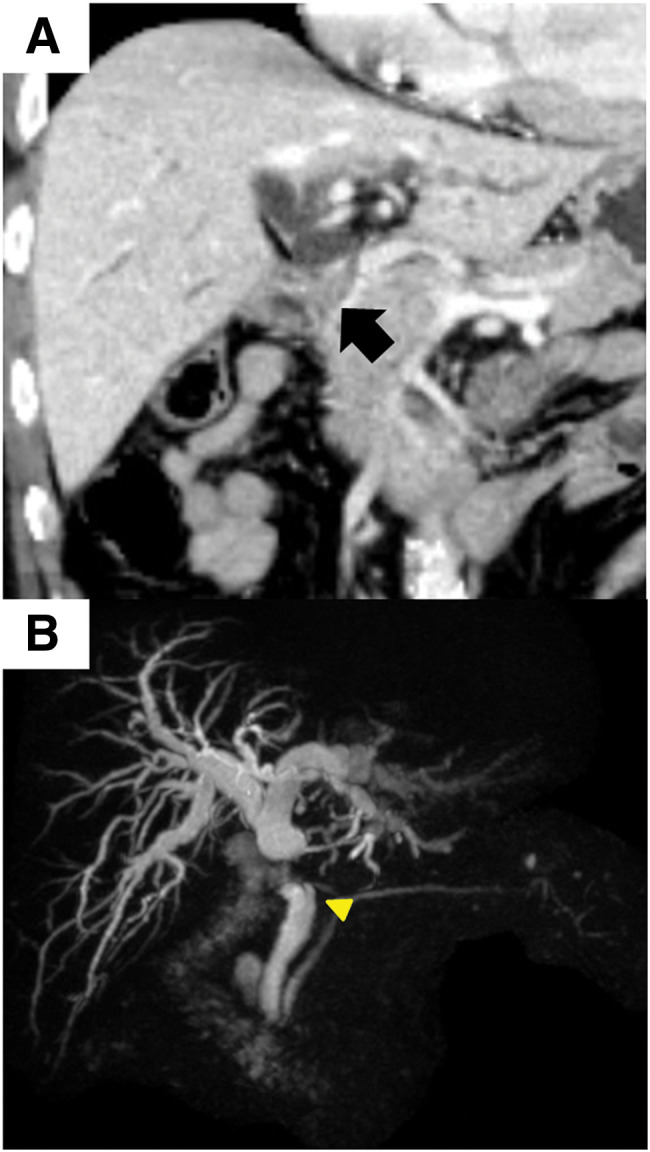

Case presentation: A 77-year-old man presented to our hospital with general fatigue and jaundice. He had previously undergone an open cholecystectomy and lithotomy for gallbladder cancer and common bile duct stones 19 years earlier. Blood tests revealed elevated levels of hepatobiliary enzymes and tumor markers. Both computed tomography and magnetic resonance imaging indicated dilatation of the intrahepatic and common bile ducts, and an enhanced nodule was observed in the common hepatic duct. Intraductal ultrasonography identified a papillary tumor infiltrating the distal bile duct from the common hepatic duct. Brush cytology subsequently helped confirm adenocarcinoma. Consequently, the patient was diagnosed with Bismuth type 1 perihilar cholangiocarcinoma and underwent subtotal stomach-preserving pancreaticoduodenectomy. Histological examination revealed the tumor as pancreatobiliary-type ICPN associated with invasive carcinoma, which had originated in the remnant cystic duct and invaded the common hepatic duct. A retrospective review of the resected gallbladder specimens from 19 years earlier confirmed ICPN according to the current classification, establishing this as a metachronous occurrence of ICPN.